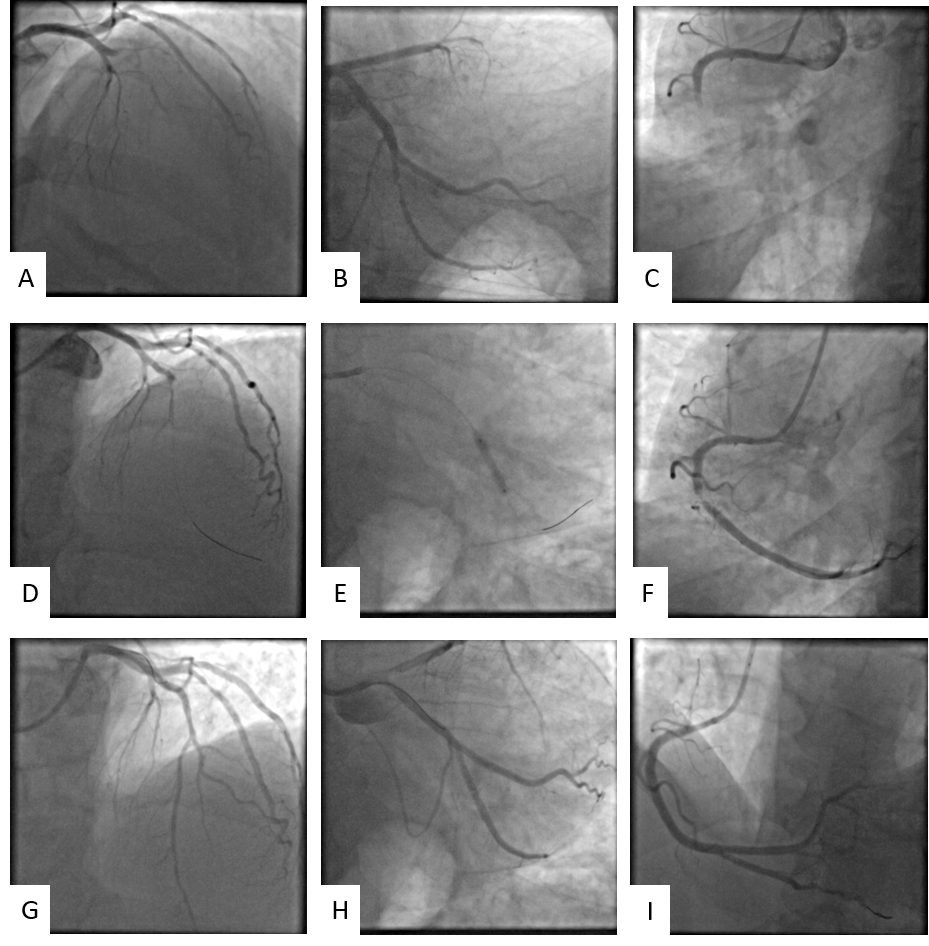

Echocardiogram showed apex, inferior wall, and inferolateral wall akinesia with moderately depressed left ventricular systolic function (ejection fraction [EF] 40%). Coronary angiography was performed via the right transradial approach and showed acute thrombotic occlusion of the mid-left anterior descending artery (LAD) (Figure 2A) and mid-right coronary artery (RCA) (Figure 2C) with Thrombolysis in Myocardial Infarction (TIMI)-flow 0 in both vessels and critical stenosis of the second obtuse marginal (OM) branch (Figure 2B).

After checking the basal activated coagulation time, UFH supplement was administered and an IV cangrelor infusion was initiated according to the patient’s weight. In consideration of the complete AV block, the RCA was treated first with angioplasty and implantation of one 3.5 x 18-mm Resolute Onyx drug-eluting stent (DES) (Medtronic) (Figure 2I). Subsequently, 2 episodes of ventricular fibrillation occurred and were treated with direct current shock at 200 J with immediate restoration of the sinus rhythm. Angioplasty and implantation of one 3.5 x 18-mm Resolute Onyx DES were performed in the mid-LAD (Figure 2D-G).

In both cases, after advancing the coronary guidewire, severe stenosis was evident after reopening the vessel. TIMI-flow 3 was reestablished in both the LAD and RCA after stent implantation.

Post-procedure, the patient was hemodynamically stable and asymptomatic. Staged angioplasty was performed with implantation of a DES on the second OM branch (Figure 2E-H). The patient was discharged with good hemodynamic compensation; ECG showed sinus rhythm and signs of previous necrosis in the inferior and anterior leads, and the echocardiogram confirmed left ventricular dysfunction (EF 40%). Dual antiplatelet therapy with acetylsalicylic acid (100 mg/die) and ticagrelor (90 mg bis in die) was initiated. In addition, pharmacological therapy for heart failure was set up and the patient was started on a follow-up and rehabilitation path. Forty days post-discharge, the patient was asymptomatic and clinically and hemodynamically stable. His left ventricular function was 45%, and ongoing therapy was confirmed.